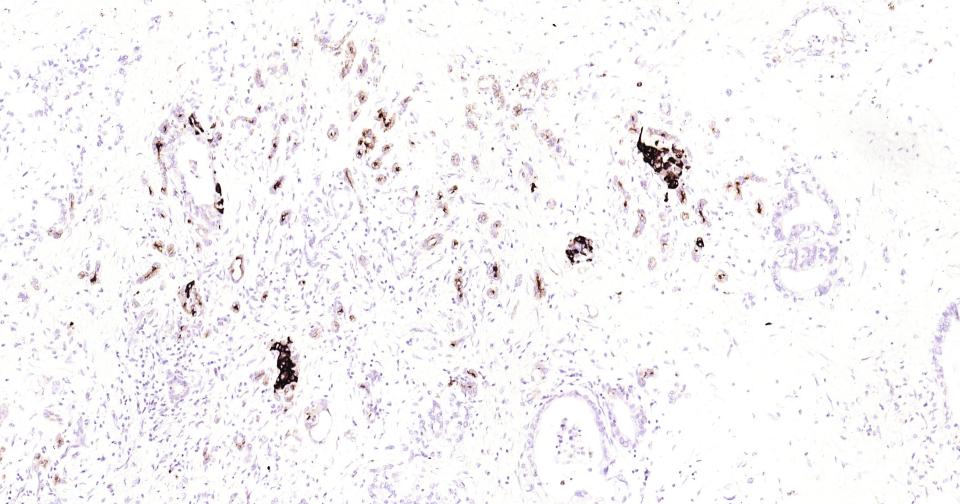

Paraformaldehyde-fixed, paraffin embedded Human Cerebrum; Antigen retrieval by boiling in sodium citrate buffer (pH6.0) for 15 min; Antibody incubation with Osteopontin? Monoclonal Antibody, Unconjugated(bsm-43600R) at 1:200 overnight at 4°C, followed by conjugation to the SP Kit (Rabbit, SP-0023)and DAB (C-0010) staining.